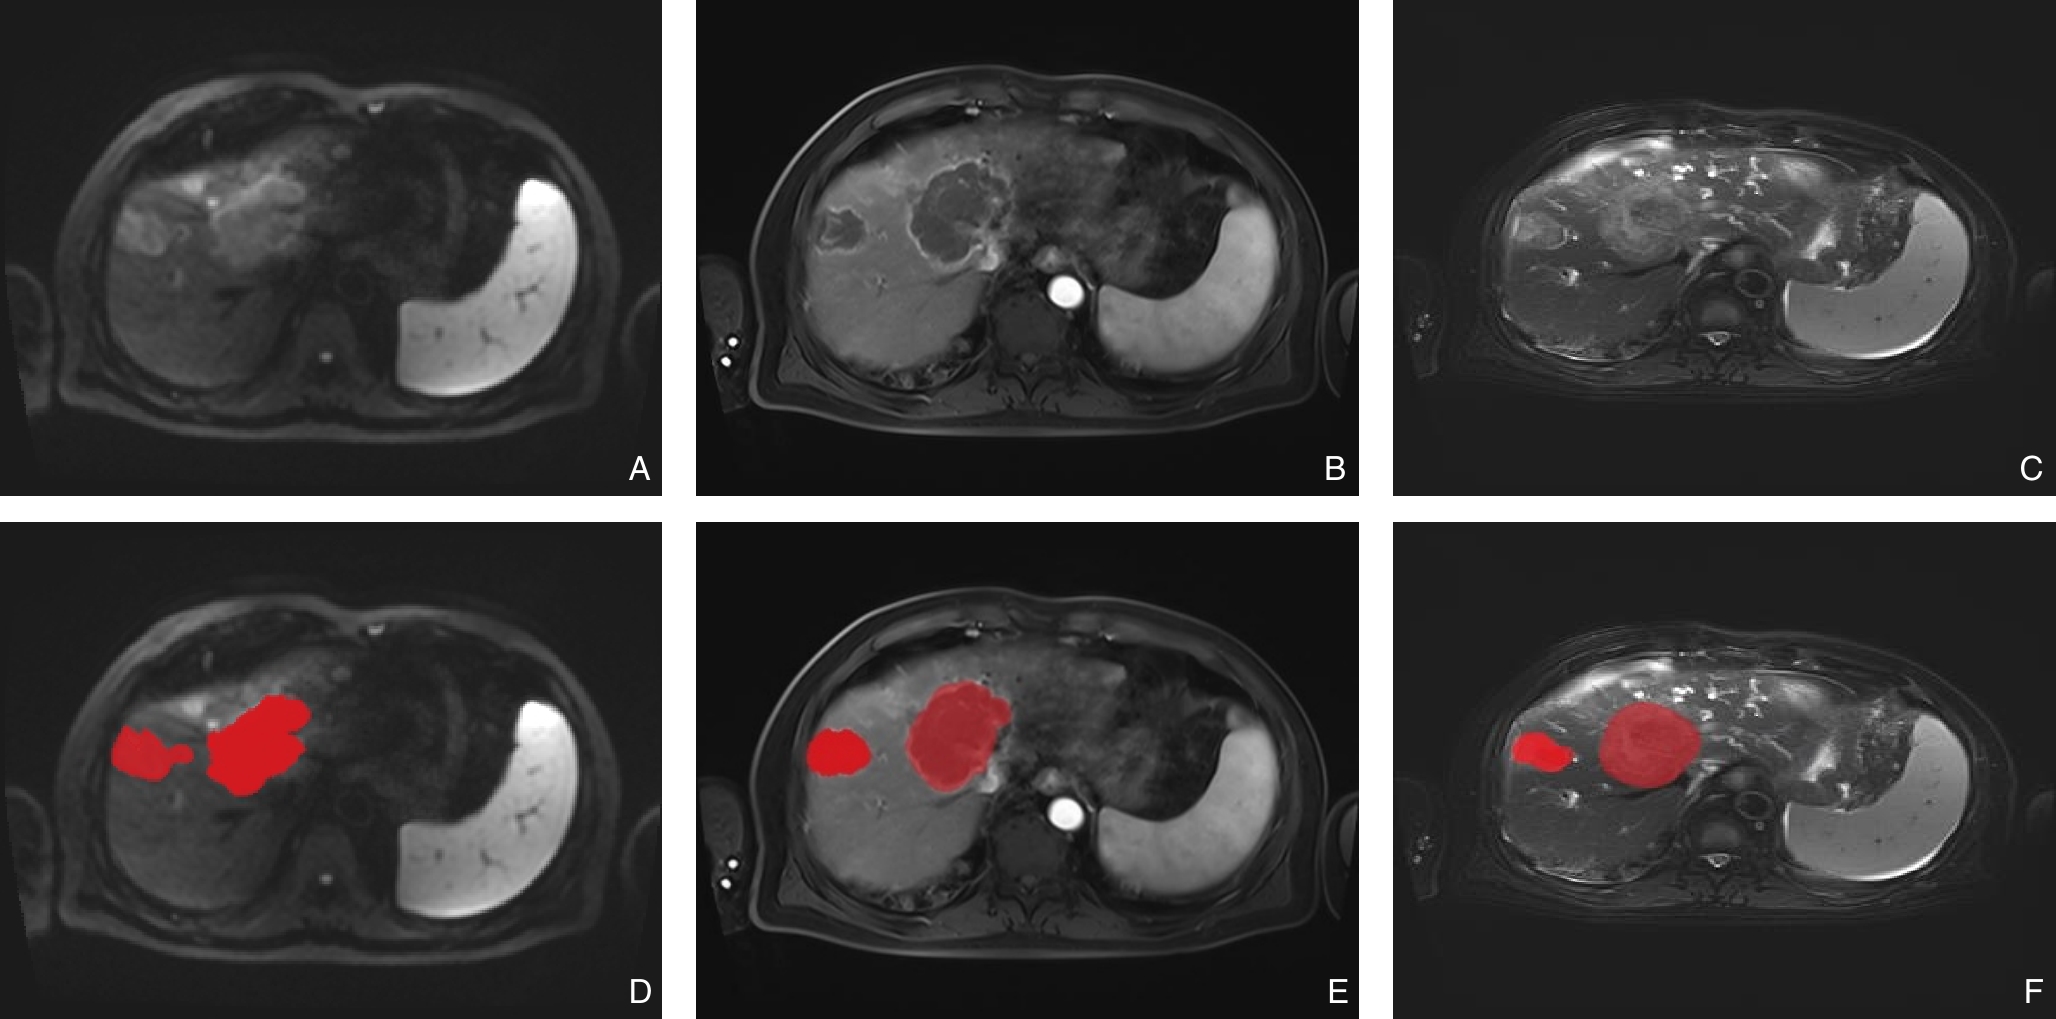

摘要:背景与目的 恶性黑色素瘤常见于皮肤及眼部等部位,肝脏原发极为罕见,且缺乏特异性临床与影像学特征,易被误诊。本文报告1例肝脏原发性黑色素瘤(PHM),并结合文献回顾分析其临床特点、诊疗策略及预后。方法 回顾性分析1例经手术切除并病理确诊的PHM患者,检索中国知网、万方、维普及PubMed数据库相关病例,共纳入42例进行总结。结果 患者,男性,61岁,术前误诊为肝细胞癌,术后免疫组化示HMB45、Melan A、SOX10强阳性,确诊为PHM。行手术完全切除肿瘤,术后12个月复发并多发转移。文献分析显示,PHM多见于中老年男性,临床表现不典型,影像学缺乏特异性,确诊依赖病理及免疫组化。预后较差,25例有随访资料的患者中,6个月和12个月生存率分别为28.00%和12.00%。结论 PHM是一种罕见且预后不良的恶性肿瘤,早期诊断困难。手术切除仍是局限性病灶的首选治疗,结合分子靶向及免疫治疗可望改善生存;失去手术机会时,应优先考虑免疫治疗和靶向治疗的个体化方案。